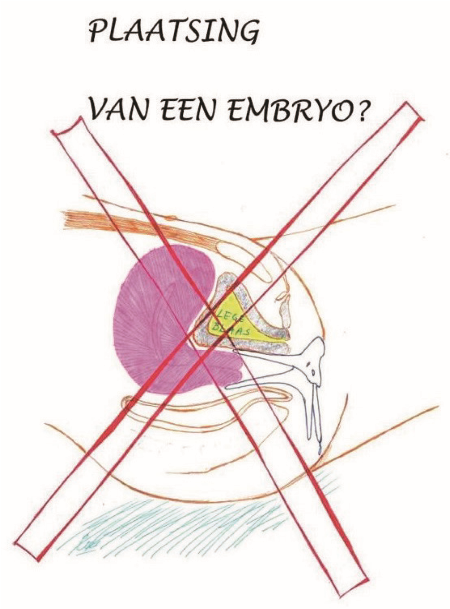

5 Plaatsing van het embryo (embryotransfer)

N.B. u dient zich beiden te kunnen identificeren voor de embryotransfer. Indien er geen identificatie aanwezig is, wordt er geen embryo teruggeplaatst.

De plaatsing is een kortdurende poliklinische ingreep waarvoor geen verdoving nodig is.

De embryotransfer vindt plaats onder echoscopisch zicht via de buik. Dit betekent dat de plaatsing met de echo via de buik gevolgd wordt om zo nauwkeurig mogelijk de juiste plaats in de baarmoeder te bepalen. Om het goed te kunnen zien, is een gevulde blaas noodzakelijk (zie 1e tekening).